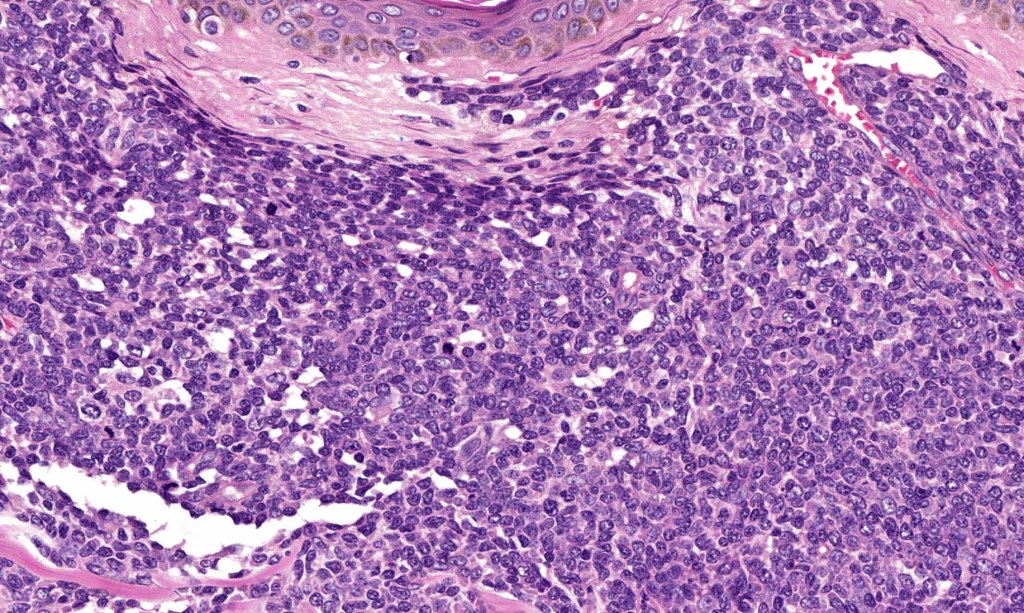

. No epidermal involvement

. Dermal +/- subcutaneous fat infiltrate

. No angioinvasion or angiodestruction

. Monotonous blast cells with gray-blue cytoplasm & irrregular vesicular nuclei with prominent nucleoli

. Marked ki67 expression